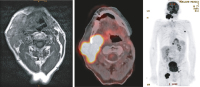

MRI - PET-CT

Abbildung 2: MRI und PET-CT. Ein MRI sowie ein 18F-FDG-PET-CT ergeben einen 6,5 cm großen Tumor am Kieferwinkel rechts mit Umscheidung der Carotis externa sowie Obstruktion der Glandula submandibularis mit deutlich glukosehypermetabolen primär malignen Lymphadenopathien rechts zervikal (Stationen 2 und 3), beidseits inguinal sowie solitär links axillär.

Keywords: Arteria carotis externaKardiologieMRIPET-CT